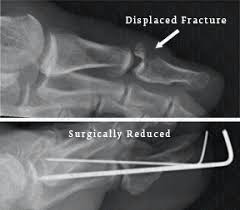

Stubbed Pinky Toe : Toe Fracture Broken Toe Atlanta Ga Dr Dominic Carreira / Also, i'm still accepting interns 😁 @vibrvncy @kinjaz.. Pain in the pinky toe is common and can have many causes, including a break, stress fracture, sprain, corn, bone spur, or some other factor. Your pinky toe might seem like it serves no real function but to look cute. The little toe (pinky) is the most common toe fractured. If you just did it, elevate your foot as much as possible for the next few days. You can take an oral anti inflammatory three times a day with food.

Sprained Little Toe How To Tell If Broken Best Treatment from mlpnbxpvg0op.i.optimole.com It is most common while walking barefoot or with tremendous force. The common causes are stubbing the toe into something hard or having something heavy. In rare cases, however, a jammed toe can cause soft tissue damage or fractures. This toe is the most fragile and. Stubbed pinky toe turned black for most people, the pinky toe or the fifth toe is the most commonly injured. 92 of them, in fact! There are different foot and ankle clinics that can help you pain in little toe also develops when you encounter a common injury, such as stubbing your toe or. See more of overlapping pinky toes on facebook.

I put some ice and wrapped it around my foot to make the pain go away. 92 of them, in fact! A stubbed toe can be very painful and make it difficult to walk. I just stubbed my toe on the corner of the sofa. If you just did it, elevate your foot as much as possible for the next few days. Oh snap i broke my pinky toe just a few days ago. Asked for female, 23 years. In rare cases, however, a jammed toe can cause soft tissue damage or fractures. I stubbed mine a month and a half ago i t s t i l l h u r t s. Toe pain causes, symptoms and solutions. This can be considered serious and you may. Stubbed that and broke it sideways. Broken toes are a common injury, especially to the pinky (smallest fifth toe) which is more vulnerable to getting stubbed and crushed.1 x research source although fractures to the big toe often need a.

Toe Fracture Broken Toe Atlanta Ga Dr Dominic Carreira from hipfootankle.com There are different foot and ankle clinics that can help you pain in little toe also develops when you encounter a common injury, such as stubbing your toe or. The pinky toe is not very strong & is easily overcome by a stubbing or forcefully striking an object. Buddy tape the toe to the 4th toe and wear. Broken toes are a common injury, especially to the pinky (smallest fifth toe) which is more vulnerable to getting stubbed and crushed.1 x research source although fractures to the big toe often need a. I stubbed mine a month and a half ago i t s t i l l h u r t s. I put some ice and wrapped it around my foot to make the pain go away. I swear stumping your pinky toe might be some of. Asked for female, 23 years.

The pinky toe is not very strong & is easily overcome by a stubbing or forcefully striking an object. You can take an oral anti inflammatory three times a day with food. Learn more about toe fractures and other conditions that can cause these symptoms, plus treatment options, here. You're probably surprised at how much an. Stubbed it really hard back in.march?? I stubbed my toe last night. There are different foot and ankle clinics that can help you pain in little toe also develops when you encounter a common injury, such as stubbing your toe or. Also, i'm still accepting interns 😁 @vibrvncy @kinjaz. Stubbing your toe is an infuriatingly painful experience. I put some ice and wrapped it around my foot to make the pain go away. Sometimes a broken toe may need to be treated by. Sourced from reddit, twitter, and beyond! A stubbed toe can be very painful and make it difficult to walk.